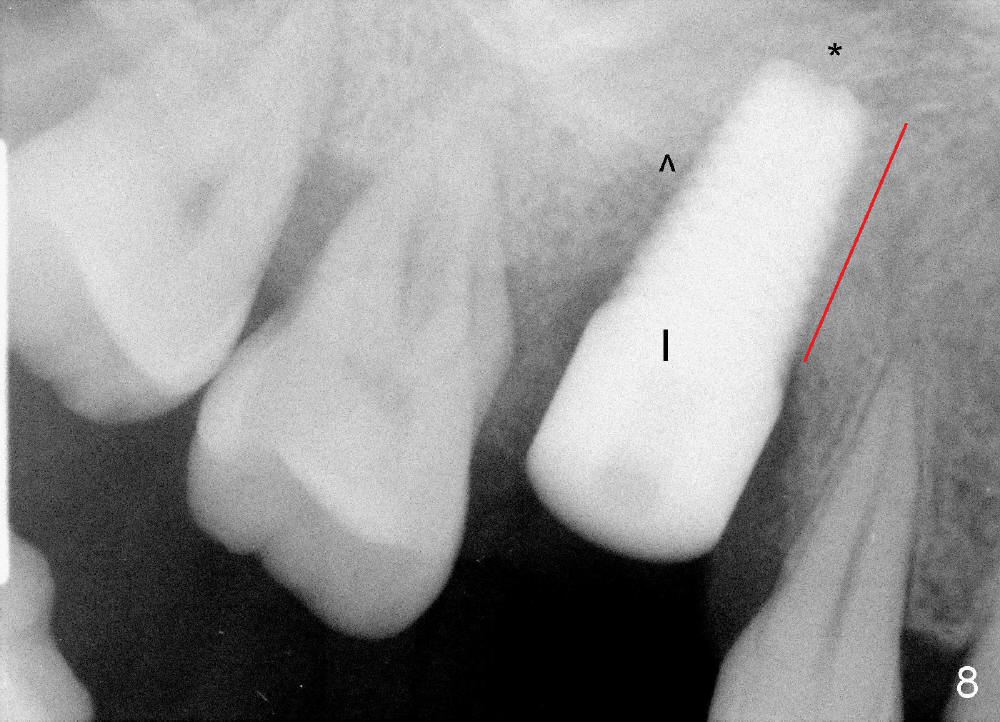

The tooth #3 has severe periodontitis with probably endodontic lesion (Fig.1,2). The patient is a 43-year-old man with apprehension of dentistry. An acute infection causes pain and tooth shift (Fig.4,5). A 7x17 mm immediate implant is planned (Fig.3). The palatal socket is shallow (Fig.6 P), corresponding to severe recessive palatal root (Fig.5 P). The osteotomy is created mainly in the buccal socket (Fig.6 B), exactly in the lingual slope of the septum. Initially osteotomes are used, followed by tap placement (Fig.7 T (4.5x20 mm at the depth of 17 mm). When the implant is placed as planned (Fig.8 I), there is more vertical contact (Fig.8 red line) than that associated with the tap (Fig.7 red line). The corresponding insertion torque is between 50 and 60 Ncm. There is only one small gap buccally, which is filled with bone graft (Fig.9 <). After the insertion of a short abutments with vertical slots (Fig.9,10 A), perio dressing is used to cover the wound. The palatal socket is expected to heal uneventfully (Fig.10 P). In fact, it does in 7 days (Fig.12 P); the bone graft in the mesiobuccal aspect is healing and stabilized (Fig.11 <). By two weeks postop, the mesiobuccal socket has healed (Fig.13 <). With removal of a diseased tooth, our body has amazing power to heal.